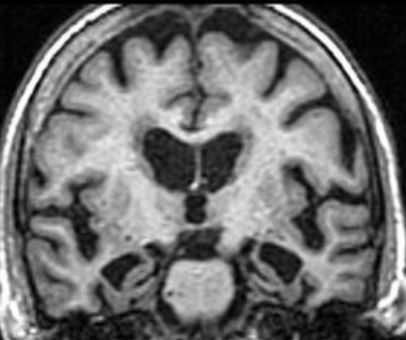

МРТ головного мозга. Т1-взвешенная корональная МРТ. Диффузная атрофия при болезни Альцгеймера.

Дифференциальную диагностику при МРТ головного мозга надо проводить с болезнью Паркинсона, мультиинфарктной деменцией и лобнотеменной деменцией (болезнь Пика).